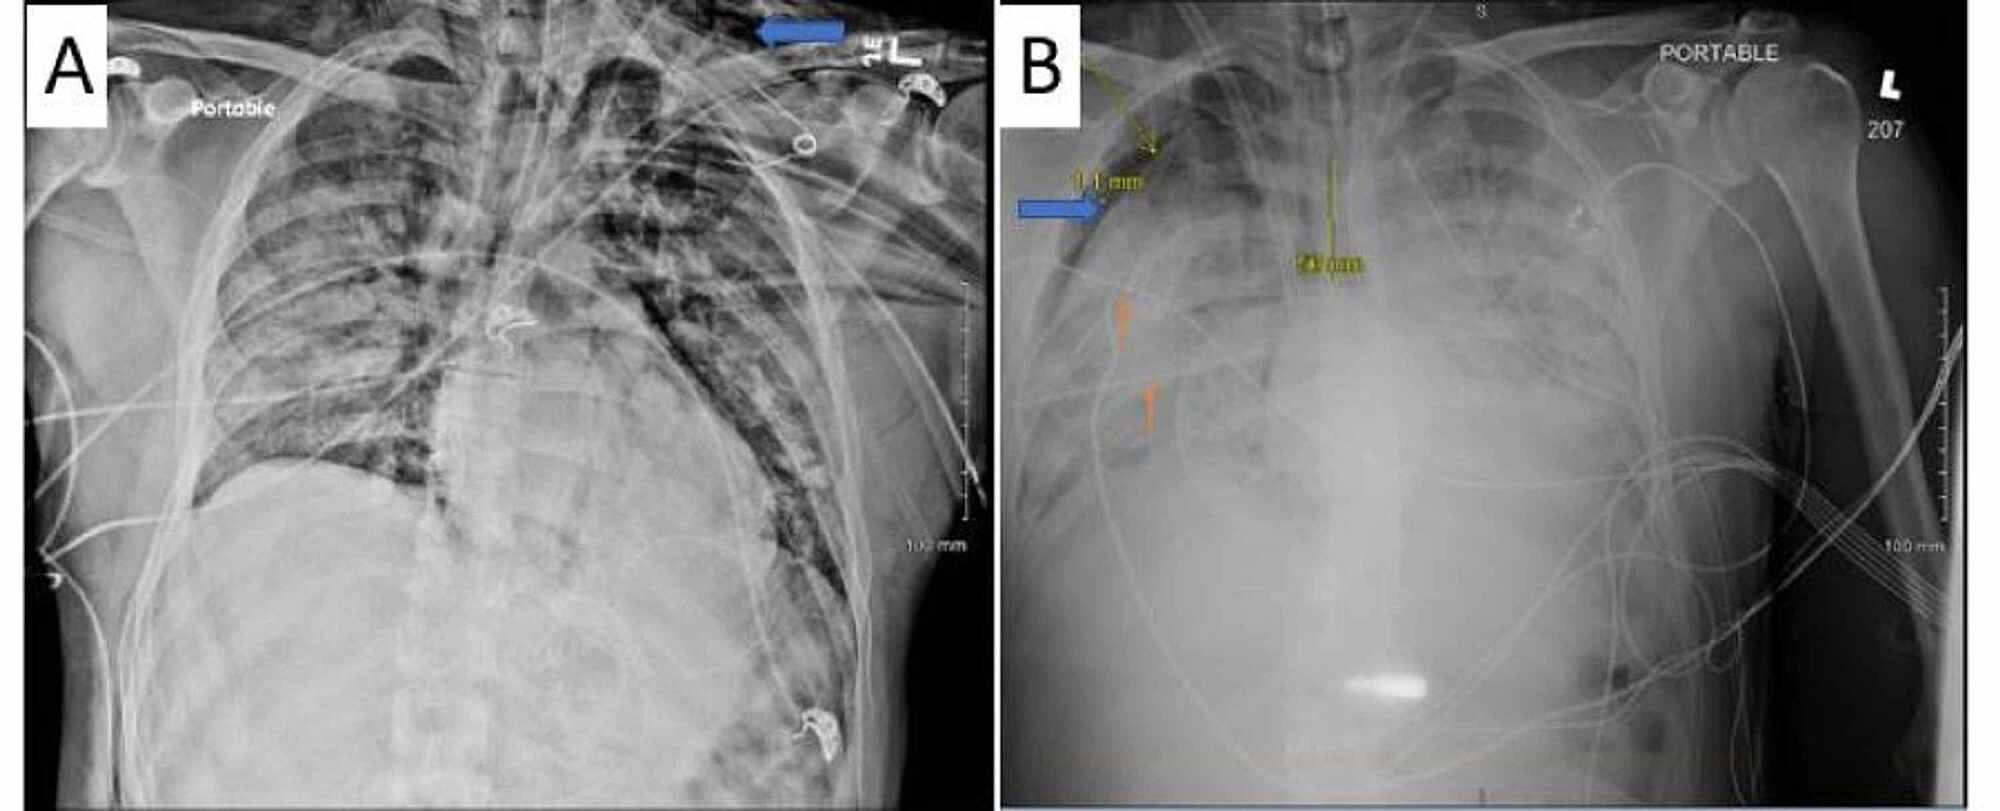

He developed worsening respiratory failure and required intubation and mechanical ventilation on admission day 3. Lung-protective ventilation was used with a positive end-expiratory pressure (PEEP) of 5 cm H2O and fraction of inspired oxygen (FiO2) 100%. His PEEP was increased to 18 cm H2O due to low arterial oxygen tension. On hospital day 5, the patient developed subcutaneous emphysema suggestive of left pneumothorax (Figure 2A) and so had a left chest tube placed. Neuromuscular blockade with cisatracurium was initiated on hospital day 6 due to persistent hypoxemia and patient-ventilator dyssynchrony. On hospital day 13, chest X-ray showed a large right pneumothorax but despite placement of two right-sided chest tubes lung re-expansion could not be achieved (Figure 2B). Arterial blood gases showed a partial pressure of oxygen (PaO2) < 60 mmHg despite an FiO2 of 100% and PEEP of 20 cm H2O. His partial pressure of carbon dioxide (PaCO2) rose above 70 mmHg with pH maintained higher than 7.30. At this point, the patient was transferred to another facility within our network with ECMO capabilities (hospital 2).